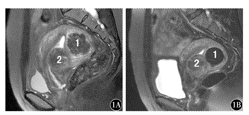

根据MRI信号特点将48个可评估肌瘤分组,行选择性UAE,本组病例均手术操作成功,未发生手术并发症,术后经抗感染及对症处理,患者恢复良好。术后分别于3、6、12个月行盆腔MRI扫描,测量肌瘤的体积大小(图1、图2)。UAE术后12个月,富于细胞性肌瘤体积缩小率高于普通未变性肌瘤和变性肌瘤,差异有统计学意义(P=0.038 ,P=0.014),而后二者之间差异无统计学意义(P=0.364)。体积≥35 cm3的肌瘤体积缩小率高于体积<35 cm3的肌瘤,差异有统计学意义(P=0.044)。黏膜下肌瘤的体积缩小率高于肌壁间肌瘤和浆膜下肌瘤(P=0.036 ,P=0.019 ),肌壁间肌瘤体积缩小率高于浆膜下肌瘤,但差异无统计学意义(P=0.384)(表1)。UAE术后肌瘤体积缩小以3个月内明显,尤其是富于细胞性肌瘤、黏膜下肌瘤体积缩小明显,达到70%左右,以后逐渐变慢,6个月以后体积缩小缓慢。黏膜下肌瘤可自行脱落,或在医生帮助下钳夹脱落,达到治愈目的。

2A:介入治疗前,子宫前壁圆形肿块影,呈等信号为主,大小5.0 cm× 5.5 cm×6.0 cm,周围环绕高信号影,子宫腔无明显受压;2B:介入治疗后12个月,肿块呈明显低信号,体积缩小,大小3.2 cm×3.5 cm×3.2 cm,体积缩小率为78.3 %